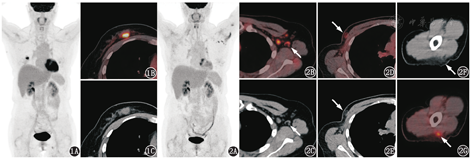

患者女,56岁,体格检查发现右乳结节,行乳腺超声及钼靶均提示乳腺恶性病变可能,拟行手术治疗,术前行18F-脱氧葡萄糖(fluorodeoxyglucose, FDG) PET/CT显像(图1)。PET/CT可见右乳内上象限代谢增高结节,大小约1.6 cm×1.4 cm,最大标准摄取值(maximum standardized uptake value, SUVmax)7.5(图1A~1C);右侧腋窝可见数个小淋巴结,形态略饱满,短径约0.4 cm,SUVmax 1.4;以上表现符合右侧乳腺癌。后患者行右侧乳腺癌根治术及腋窝淋巴结清扫术,术后病理示右侧浸润性乳腺癌,伴右腋窝1枚淋巴结转移,术后辅助内分泌治疗。

术后半年患者自行触及右侧胸壁结节,为明确全身情况再次行18F-FDG PET/CT显像(图2)。术后PET/CT见左侧腋窝多发代谢增高的淋巴结,短径约0.3~0.8 cm,SUVmax 1.8~4.4(图2A~2C);右侧胸壁皮下可见代谢稍高影,SUVmax 2.2,同机CT上呈片状稍高密度絮状影(图2D,2E)。

结合患者右侧乳腺癌病史、新见对侧腋窝多发代谢增高淋巴结,首先考虑转移淋巴结的可能。但若仔细观察左侧腋窝淋巴结的形态,会有几点疑问:(1)在左侧腋窝代谢增高的淋巴结中,部分淋巴结仍具正常形态,淋巴结门结构清晰可见(图2B,2C,箭头示),提示其可能为良性淋巴结。若考虑早期转移可能肿瘤组织很少,未影响到淋巴结形态结构的改变,则又与其增高的代谢程度不甚相符。(2)对比术前PET/CT,左侧腋窝淋巴结的数量没有增加,只是部分淋巴结体积较前增大;而具有正常淋巴结门结构的几枚淋巴结的大小、形态较术前没有明显变化,只是代谢较前明显增高(图像未显示)。(3)患者触及的右侧胸壁结节,在PET/CT上表现为代谢轻度增高的小片絮状影,不是实性的软组织结节(图2D、2E,箭头示),不支持该胸壁结节是肿瘤复发灶。以上几点影像特征支持良性病变的可能性大于恶性病变,但考虑到患者有乳腺癌病史,直接诊断左侧腋窝淋巴结为良性证据不足;但如果漏诊或误诊恶性病变,会延误患者病情,后果可能更严重。

引起淋巴结FDG代谢增高的良性疾病多见于感染[如结核、Epstein-Barr病毒(Epstein-Barr virus, EBV)感染]、自身免疫性疾病[如免疫球蛋白(immunoglobulin, IgG)4相关疾病、结节病]、反应性增生等。根据该例患者的病史和PET/CT表现,并未见以上病因的蛛丝马迹。再仔细观察PET/CT图像,发现左上臂三角肌部位的皮下脂肪内见片絮状的代谢稍高影(图2F、2G,箭头示)。该类表现在阅片时易被忽略,或直接判断为肌肉局灶性的生理性摄取或皮下和(或)皮肤组织非特异性炎性病变,大多没有临床意义。然而对于本例而言,该处病变距离腋窝近,且为同侧,如果此处是明确的炎性病灶,则可以解释左侧腋窝出现代谢增高淋巴结的原因。